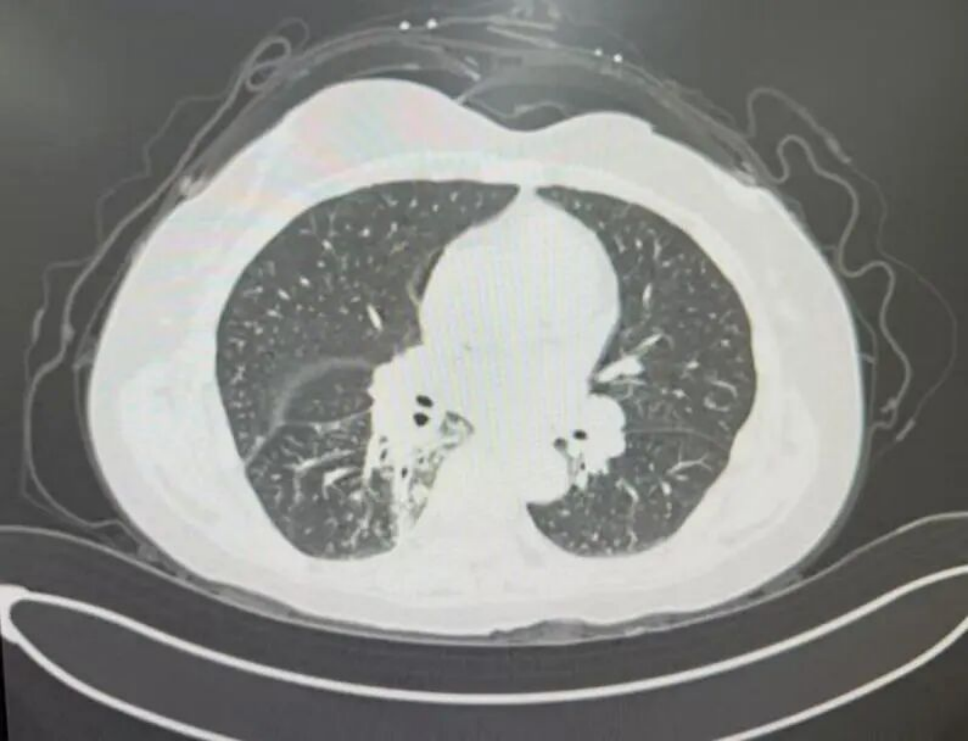

*患者胸部CT

先天性食管气管瘘为临床罕见的疑难危重症疾病,该疾病手术难度大、术中风险高。胸部外科立即启动MDT多学科诊疗,为马阿姨的手术保驾护航。